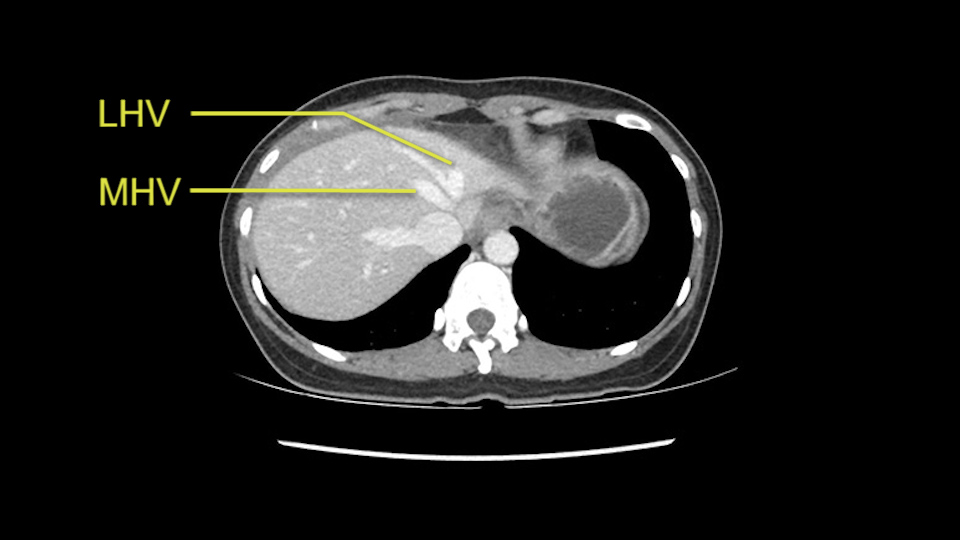

Anatomically, to plan for a left lateral segmentectomy, it’s relatively easy as far as liver surgery goes. I know that I'm going to be looking for the left hepatic vein which will be divided at some point either towards the end at the back near the vena cava or through the middle of the left lateral segment.

The transection line will be a little more obvious. There’s a little patch of focal fat here in Segment 4b but we’ll describe the transection line probably through the mid portion of Segments 4a and b up to the top. Up at the top, the left hepatic vein can be taken. There’s a Segment 3 vein or the so-called falciform vein it’ll be rudimentary so I think we’ll be able to get around the left hepatic vein and leave the middle [hepatic] vein intact because it’s free of tumor.

Her vein, it looks like a combined middle and left hepatic vein, it may be encircled during the case as a whole common trunk but most probably it will not be a big deal because if it is okay to go with the left lateral resection, the vein or the left hepatic vein can be catched during the intraparenchymal dissection and can be controlled in that side.

The cava however is again displaced by this well encapsulated mass, so I would expect that I should be able to lift out of the cava with some moment of careful dissection and the cava is not infiltrated by this tumor. Most of the tumor is below the portal plane and the hepatic-venous vein is completely free. You have the left and the middle hepatic vein joining together and opening up. The right hepatic vein is as usual. All the superior segments of the liver are intact so we do not expect any major problem in this particular case as far as the venous outflow is concerned. So this is about the preoperative planning as far as this case is concerned.

The other option of course is to do an anatomical left hepatectomy. In that case, I will start mobilizing of course the left lobe and try to find the ligamentum venosum, take it down and go around the left hepatic vein. I think, importantly in these cases and in this case, as you can see in the venous phase, that’s clearly a moment to stop. Because the left hepatic vein is pretty close to the middle hepatic vein as sometimes it is so you may need to dissect a little bit the parenchyma on top of the left hepatic vein to be able to go around the left hepatic vein safely.